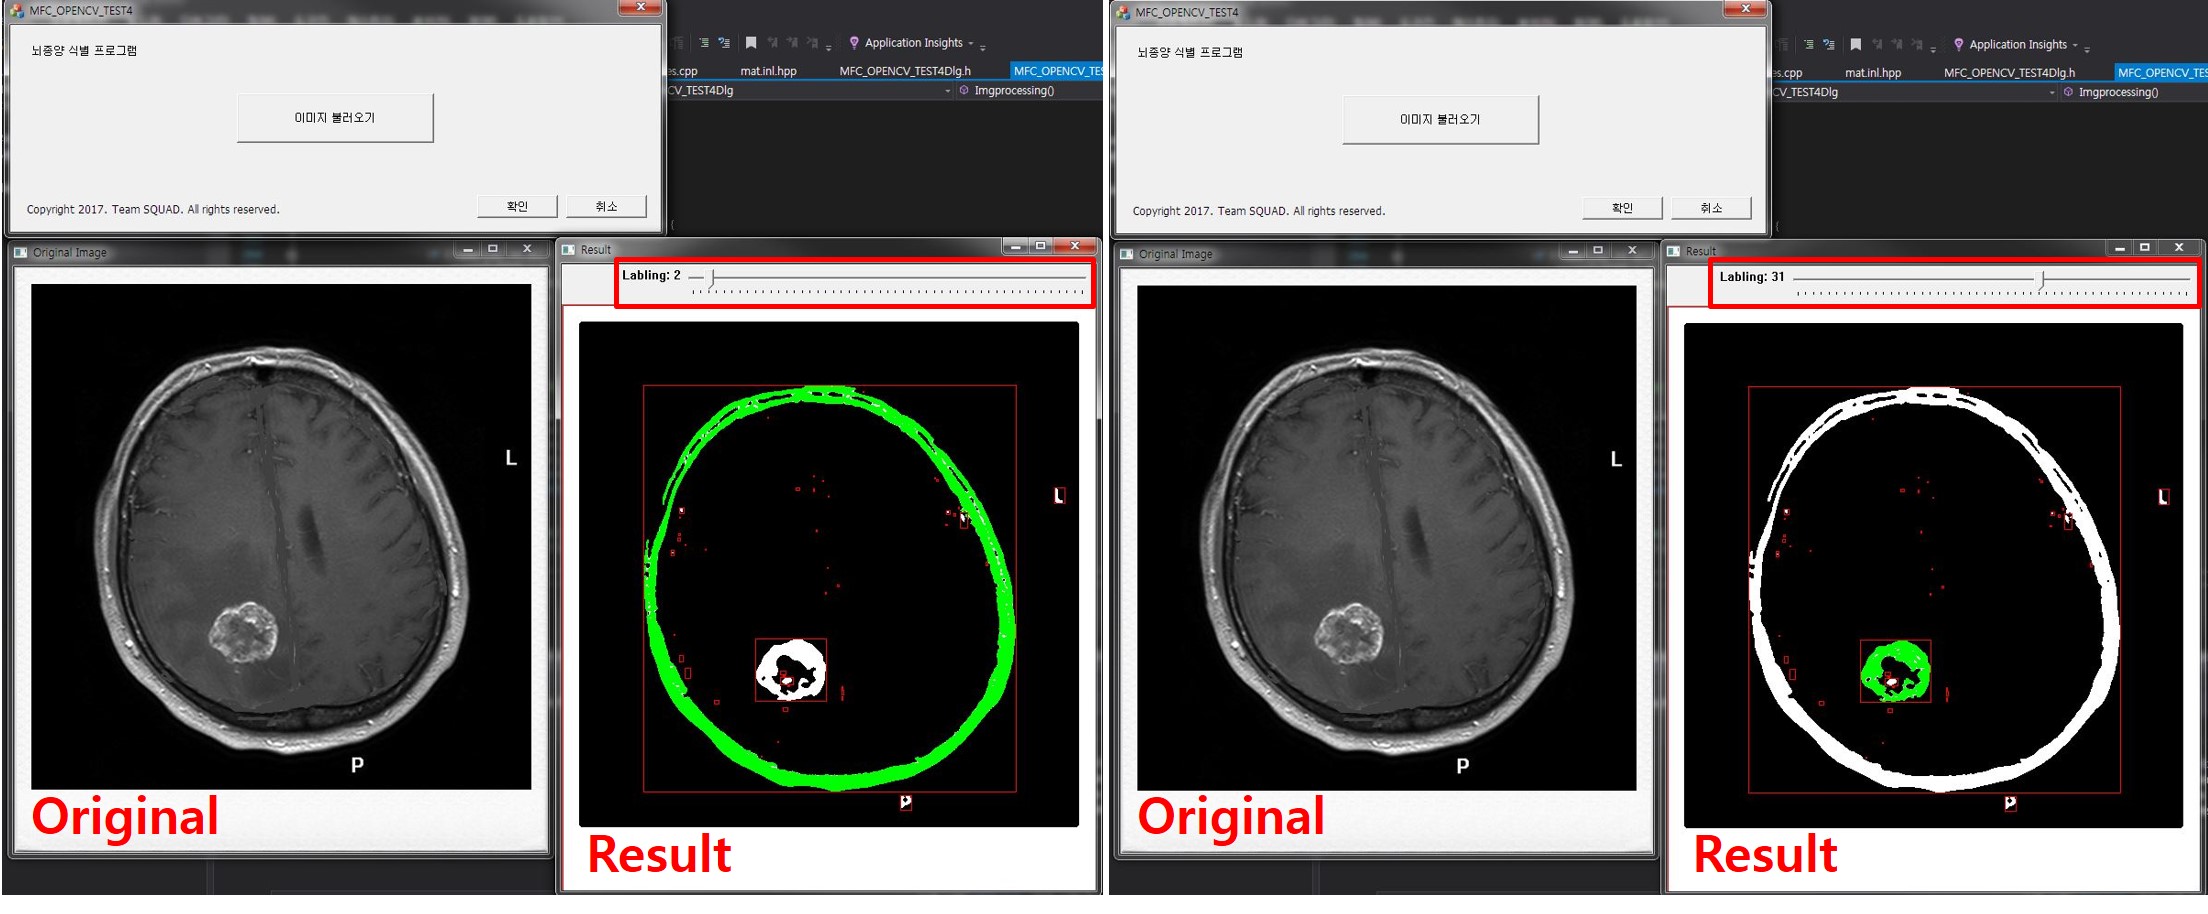

이미지처리를 이용해 DICOM 영상에서 뇌종양 부위 식별에 도움을 주는 알고리즘을 개발함. DICOM 영상데이터를 OpenCV에서 처리가능한 데이터로 변환하고, 이진화 및 모폴로지를 통해 전처리함. 실제 뇌종양 영역의 데이터 분포와 비슷한 양상의 영역을 후보군으로 검출하여 뇌종양 영역 식별을 용이하게함.